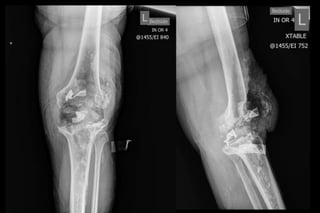

68 yo male

6 weeks postop